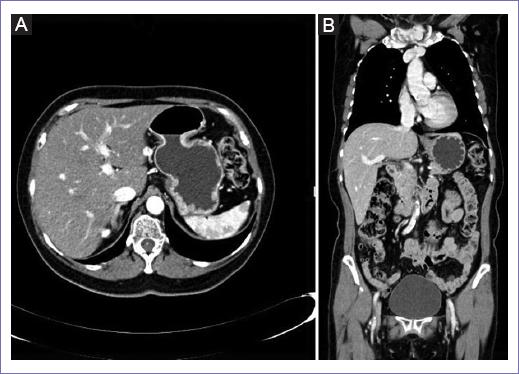

La tomografía computarizada (TC) torácica, abdominal y pélvica no mostró datos de actividad tumoral en región abdominal ni retroperitoneal, solo mostró un quiste simple dependiente del anexo derecho y aumento de reforzamiento en la región del cérvix con extensión al canal vaginal del lado izquierdo (Figs. 1 y 2). Así mismo, se realizó un ultrasonido endovaginal documentando un útero de 46 x 17 mm, endometrio lineal, cérvix sin alteraciones, anexo derecho con imagen anecoica, bien delimitada de 2 x 2 cm avascular y anexo izquierdo sin alteraciones.

Figura 1 A: plano axial de la TC. B: plano coronal de la TC, donde no se observan imágenes sospechosas de actividad tumoral a nivel torácico abdominal.